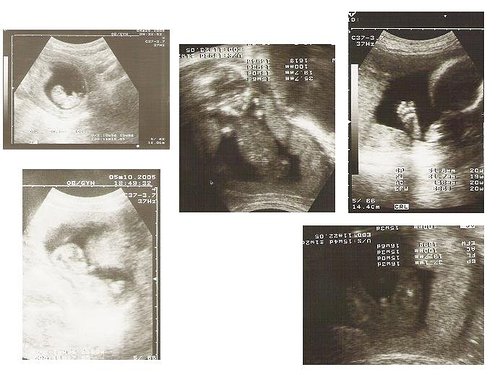

以前沒概念,還以為小孩在肚子裡成長的順序是手腳一隻一隻慢慢長出來。錯錯錯!左上角大約是二個多月時,大小為12公分左右,已經可以看到人類外觀的雛形,這張二個多月時的照片,是從北鼻的側面拍,圓圓的大頭和微微翹起的腳丫...

左下那張更明顯了,也是側身照,微微可看到手手舉起...

中間那張北鼻其實是倒立的,為了不讓觀眾脖子扭到,已經轉了180度。呵呵....沒錯,他嘴巴好像笑成了三角形。

右上角不用多說,就是他的小腳ㄚ,五根腳趾頭根根分明....

最後,右下角那張就是壓軸了。好吧,我說明一下,當時就是這張照片告訴我,我們家來了一位弟弟。看出來了嗎?是從屁屁的角度照的,中間那個東東不用我說了吧,就是「大雕」啦!